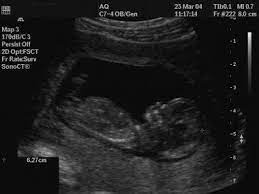

What Is A Third Trimester Pregnancy Growth Scan

What Is A Third Trimester Pregnancy Growth Scan from www.bounty.com